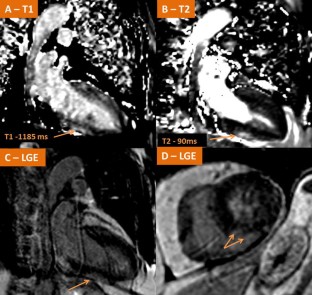

Figure 2